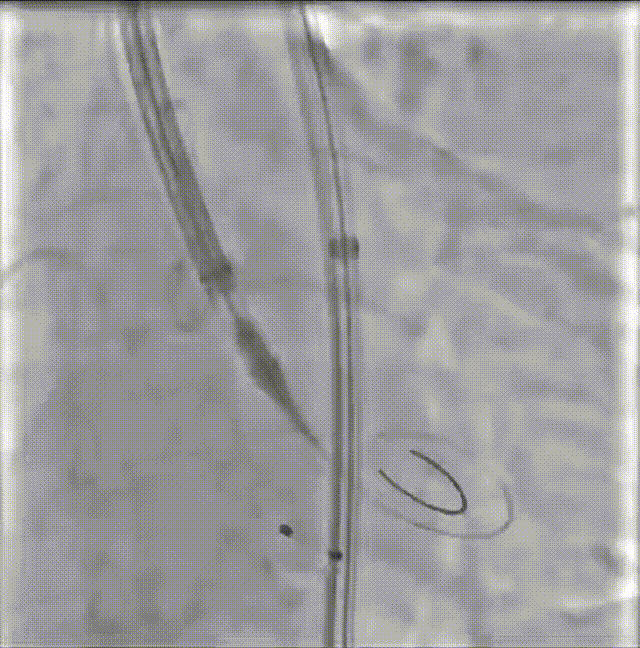

修建成教授 南方医科大学南方医院(点击查看专家详细简历) 细微之处防未然,创新携手寸寸安: 愈知临床无小事,任何风险的蛛丝马迹,都可能牵动全局。我常对团队说,真正的严谨,是将所有潜在 scenario 视作必然,在术前便一一拆解、化解 —— 如同在堤坝溃决前便筑牢每一寸基石,让风险连萌芽的机会都没有。 此次应用全球首创的预装干瓣,是基于对患者的综合考量,拥抱创新,实践创新,让创新携手助力“万全之策”的重要环节。 术前推演需要结合器械的特性:深度了解才能得心应手,结合患者基础病的相互影响并落实到术后 72 小时的并发症预警,每个环节都要像精密齿轮般咬合无误。这份 “穷尽万一” 的准备,从来不是对完美的苛求,看似耗时费力,实则是对生命最质朴的承诺 ——以医者的周全,携手创新的产品,为患者的万无一失不断努力! 患者病史 因 "反复胸闷伴活动后呼吸困难 3 年" 入院:患者 3 年前无明显诱因反复出现胸闷,部位在前胸,有憋气感,间有心悸,伴有活动后呼吸困难;外院就诊,查心脏彩超示 "主动脉狭窄、二尖瓣关闭不全"; 既往有高血压 20 余年,长期服用氨氯地平阿托伐他汀钙片降压治疗;有糖尿病 1 年,长期服用二甲双胍、阿卡波糖降糖治疗。 术前超声提示:主动脉瓣增厚、钙化并狭窄(重度)及关闭不全(轻度) 术前超声提示:主动脉瓣增厚、钙化并狭窄(重度)及关闭不全(轻度) 术前CT Type1型(R-N)二叶瓣,中度钙化集中在左窦瓣叶边缘及右无交界处,主动脉根部直径21.6mm,LVOT直径22.2mm,瓣上限制逐渐增大;双侧冠脉开口高度可,瓣叶短,窦部宽度足够,双冠VTC空间>4mm,预估冠脉风险小。 左室腔小,室间隔膜部短,有一定PPI风险;外周双侧入路无明显迂曲,双侧髂外动脉存在散在钙化、股动脉直径大,右股低分叉,能够支持20F大鞘通过。 手术策略 推荐右侧股动脉为主入路,放置20F大鞘,左侧为辅助入路,常规穿刺;使用20球囊预扩,预装AV23瓣膜;左右重叠位:RAO 1° CAU 28° ;右窦居中位:LAO 22° CAU 0° ;左冠切线回调:LAO 35° CRA 17° ;心室小,术前术中积极补液调整容量,做好循环崩溃处理准备。 手术过程 主动脉根部造影 20mm球囊预扩 - 无腰无漏 瓣膜初始定位 工作位观察瓣膜 - 冠脉通畅,位置合适 最终造影观察 - 无瓣周漏、挂钩处于最右方-Commisural Alignment 术前压差120mmHg,术后压差2mmHg。 Prostyle A®预装干瓣——助力临床最优化解决方案: 平衡的径向支撑力:该病例为TYPE 1型二叶瓣,对产品的径向支撑力是一种考验,术后影像彰显Prostyle A®综合设计带来平衡的径向支撑力,轻松应对高钙化病变,符合中国国情,为二叶瓣患者带来信心保障; 轻松过弓,精准可控:该病例主动脉弓角度可,但弓距小,考验产品的通过性能,术中顺利过弓,未使用snare轻松过弓; 预装干瓣 便捷顺安:金仕生物专利抗钙化技术运用纳米技术去除组织内的细胞碎片和磷脂,封闭游离醛基,从根本上阻断了瓣膜钙化的多项因素,显著提升了瓣膜的耐久性;同时,相比较传统戊二醛保存方式,干式存储最大限度的保留心包的亲水亲油平衡,还原组织天然曲柔性,进一步保障了瓣叶开合,保证长期耐久性。